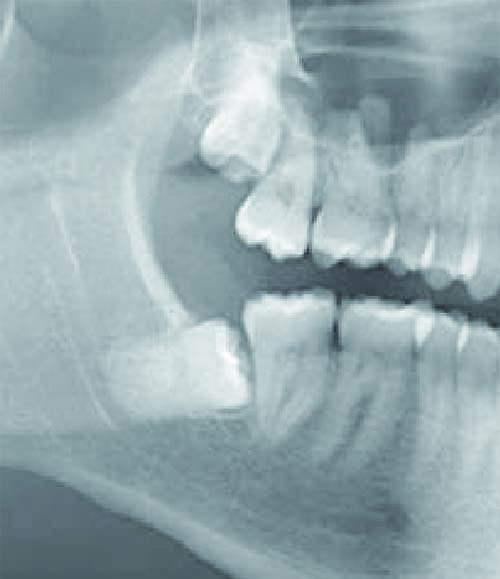

Abbildung links

linke Abbildung: Im Knochen retinierte Weisheitszähne im Ober- und Unterkiefer. Die Krone des Weisheitszahnes liegt hier unmittelbar am zweiten Backenzahn. Der Zahnhalteapparat des benachbarten Zahnes wird so auf Dauer erheblich geschädigt.